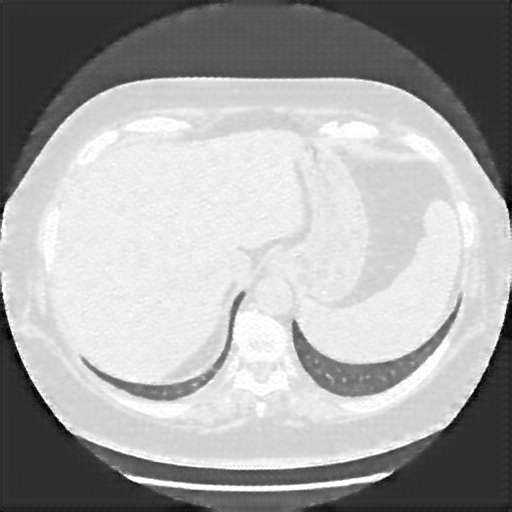

Generated VENOUS CT scan (A→B translation)

Lung window (WL -600, WW 1500 β†’ Low βˆ’1350, High +150)